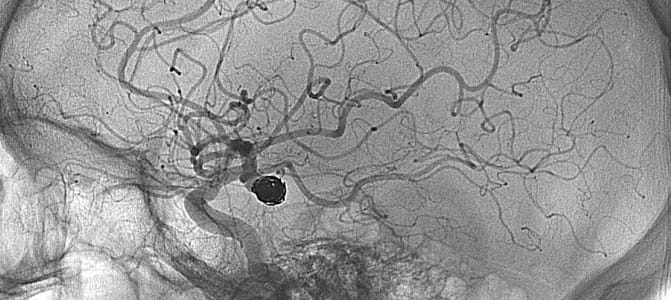

Less sophisticated devices tested previously produced disappointing results in clinical trials. But the new studies tested more modern devices such as a retrievable stent, a tiny wire cage attached to a catheter that is threaded through an artery in the groin to the blocked artery in the brain. The stent opens and traps the clot, allowing doctors to extract the clot and reopen the artery nearly every time.

Among the new research is a Canadian study known as ESCAPE that involved 315 stroke patients. Most were given the clot-busting medicine tPA, and about half of them were also treated with a clot removal device.

Three months after their strokes, 53 percent of patients whose treatment included clot removal were functionally independent and able to take care of themselves compared with about 29 percent given tPA alone. The treatment also improved the odds of survival. In the clot-removal group, about 90 percent of patients were still alive after three months compared with 81 percent in the tPA-alone group. The results(link opens in new window) were published simultaneously in the New England Journal of Medicine.

Results were similar in a smaller Australian study called EXTEND-IA, also published(link opens in new window) simultaneously in the New England Journal of Medicine: 71 percent of stroke patients given both treatments were functionally independent after three months compared with 40 percent of those given tPA alone.

Another study, dubbed SWIFT PRIME, involved 196 stroke patients in the United States and Europe. Researchers found that 60 percent given both treatments achieved functional independence three months later compared with about 36 percent given tPA alone. There were also fewer deaths among patients who had their clots removed: 9.2 percent versus 12.4 percent.

Saver added that about 60,000 American stroke patients each year may be eligible for the new therapy. In all three studies, the clot was removed from the blocked artery within six to 12 hours after stroke symptoms started. Researchers used simple imaging to quickly assess whether a stroke patient had a large clot.